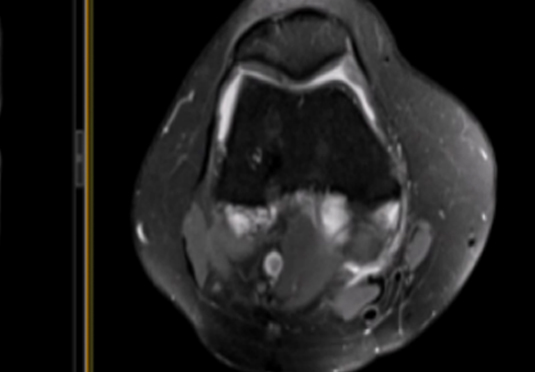

微創(chuàng)射頻消融術

適用于微創(chuàng)射頻熱消融術治療患者,引進權威醫(yī)療團體輔助引流。